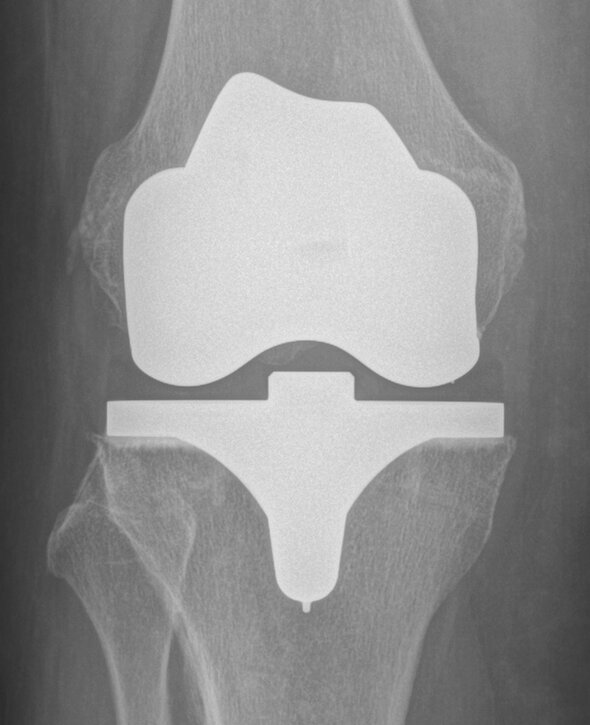

X-ray check

An X-ray is taken to see how the prosthesis is seated. This X-ray image serves as a reference for follow-up exams.